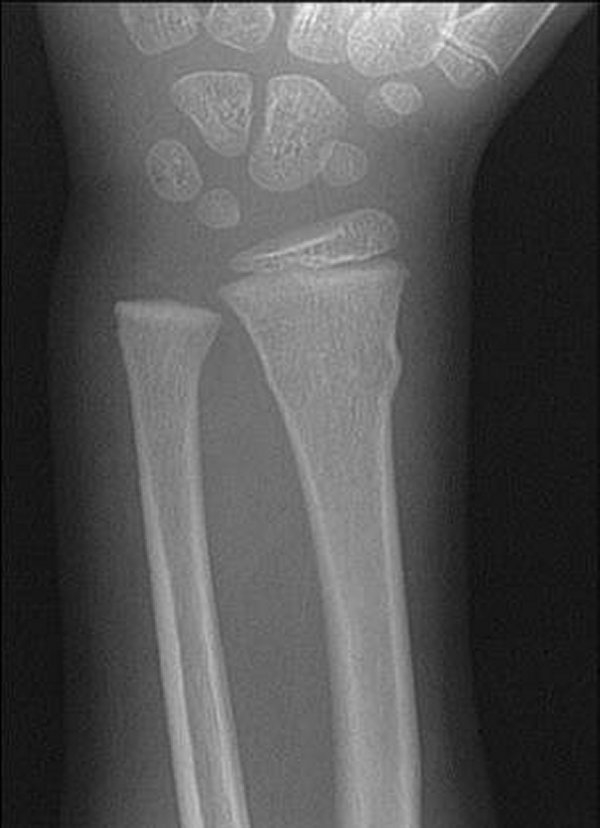

What is going on in this hand/wrist x-ray?

Taurus fracture or Buckle fracture

Common in kids and adolescents where the periosteum is stronger than the bone. More than half of these fractures involve the metaphysis only.

Any cortical “bump” should be considered a Taurus fracture if the kid has symptoms at the site.

Tx for nondisplaced fractures: splint of < 48 hours old, cast for 2-4 weeks if > 48 hours old. Repeat radiography is not indicated if symptoms improve.